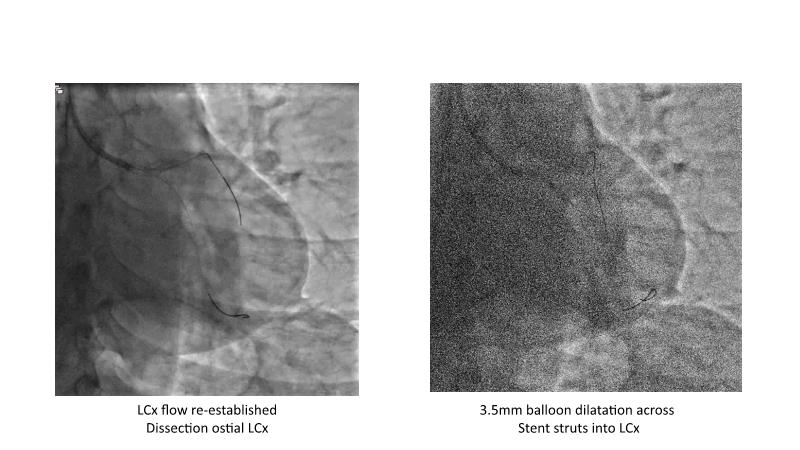

This session is recommended for you if you are seeking insights into the advantages of using IVUS imaging over visual assessment for better outcomes in left main bifurcation procedures. Discuss with experts the benefits of using RotaCUT in lesion preparation for left main bifurcation and explore the impact of high radial strength stents on the procedure's success.

• To see advantages of RotaCUT as part of lesion preparation in left main bifurcation